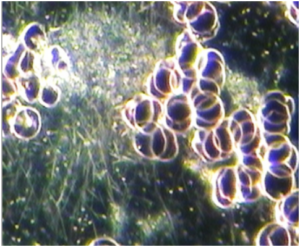

Increased risk of thrombosis is indicated by the presence of the following 3 anomalies in the working area of the sample:

- Rouleau and/or RBC aggregation

- Thrombocyte aggregation

- Fibrin (diffuse)

This combination of anomalies is suggestive of increased blood viscosity and is associated with an increased risk of thrombosis and thromboembolism (blood clots). This is a potentially serious finding and correlates with conditions related to blood vessel obstruction, tissue hypoxia (under-oxygenation) and cell death as seen in heart attacks and strokes. It is also often observed in patients with deep venous thrombosis (DVT). High doses of omega-3, vitamin E and Lumbrokinase (Lumbrozyme) / Nattokinase is helpful to address this anomaly, which is often the highest priority to address when observed.